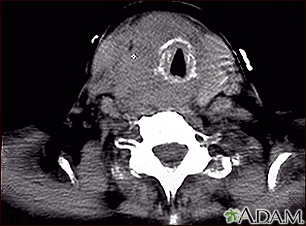

Thyroid cancer - CT scan